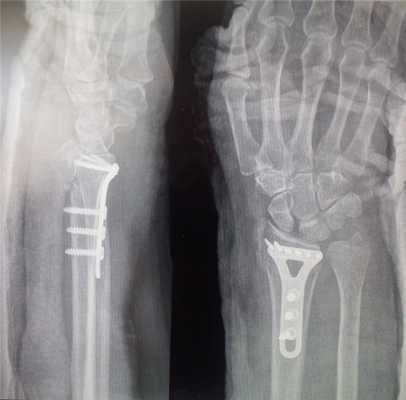

Открытая репозиция перелома лучевой кости

Открытая репозиция накостный остеосинтез пластиной и винтами. Операция включает в себя хирургический разрез, доступ к сломанной кости аккуратно отводя сухожилия, сосуды и нервы, мобилизацию костных отломков, устранение смещения и фиксация в правильном положении. Сломанные кости фиксируются титановыми пластинами, ввиду этого пациенту разрешается ранняя разработка движений в лучезапястном суставе.

Остеосинтез лучевой кости пластиной

При значительном смещении отломков используется остеосинтез лучевой кости металлической пластиной, специально изготовленной для данного сегмента. После сопоставления отломков пластина фиксируется винтами к поврежденной кости. После установки пластины накладываются на кожу накладываются швы на 2 недели, а также гипсовая лонгета примерно на тот же срок. После операции назначается лекарственная терапия: обезболивающие препараты, препараты кальция для более быстрого срастания костей, при необходимости - препараты местного действия для уменьшения отека. Средний срок пребывания в стационаре - 7 дней. Швы снимаются в амбулаторном режиме спустя 2 недели. Рука носится в возвышенном положении на косыночной повязке. Необходимости в удалении пластины нет.

До операции:

После операции:

После операции